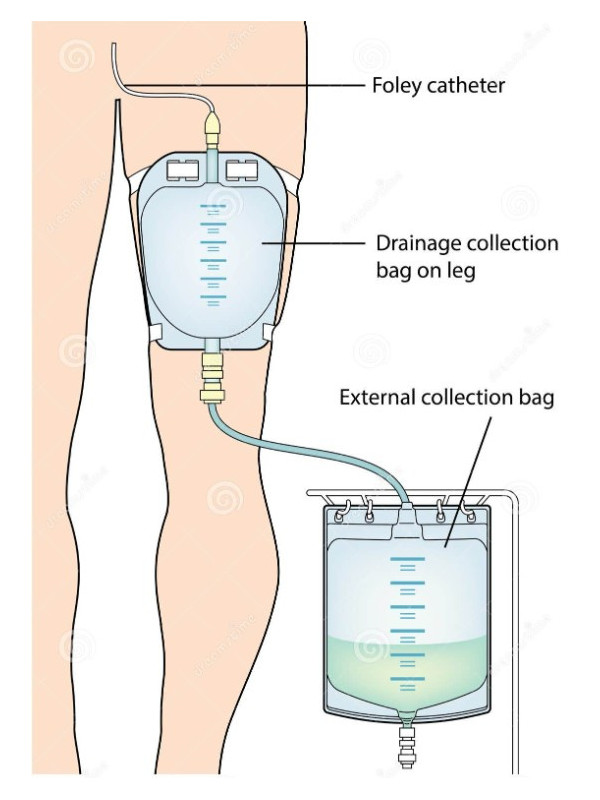

Worek QUFORA® 11061901 do Zbiórki Moczu 350 ml Mocowany na Nogę - Komfort i Bezpieczeństwo dla Pacjentów z Cewnikiem lub Urostomią

Przeznaczony dla osób z cewnikiem lub urostomią, worek do zbiórki moczu firmy Qufora jest idealnym rozwiązaniem dla pacjentów wymagających niezawodnego i komfortowego systemu zbiórki moczu. Produkt ten jest refundowany w przypadku urostomii, nadpęcherzowego odprowadzania moczu oraz nefrostomii.

- Długość drenu: 30 cm

- Rodzaj worka: na nogę

- Gładki dren o dużej średnicy: Dren (przewód) jest elastyczny, gładki i stabilny, co umożliwia swobodny przepływ moczu. Dzięki dużej średnicy eliminuje ryzyko niedrożności oraz zatkania, zapewniając niezakłócony odpływ moczu. Możliwość docięcia drenu pozwala na dostosowanie jego długości do indywidualnych potrzeb użytkownika.

- Elastyczny i miękki dren: Dren jest dyskretny, miękki i elastyczny, co pozwala na pełną swobodę ruchu. Dzięki temu użytkownik może swobodnie poruszać się z workiem, nie obawiając się o jego widoczność czy niewygodę. Możliwość umiejscowienia worka poniżej poziomu pęcherza moczowego ułatwia naturalny odpływ moczu, bez zalegania kropli.

- Przystosowany do noszenia na udzie lub łydce: Worek jest zaprojektowany z myślą o dyskretnym noszeniu na udzie lub łydce, co pozwala na wygodne i niewidoczne pod ubraniem umiejscowienie worka. Paski mocujące zapewniają stabilność i bezpieczeństwo podczas codziennych czynności.

- Bezpośrednie podłączenie do worka nocnego: Dren wychodzący z worka może być bezpośrednio podłączony do większego worka nocnego, co eliminuje potrzebę zdejmowania worka zamocowanego do nogi na noc. To rozwiązanie jest szczególnie wygodne dla osób, które muszą korzystać z worka przez całą dobę.

- Gładki dren o dużej średnicy: Elastyczny i stabilny dren zapewnia swobodny przepływ moczu, eliminując ryzyko niedrożności oraz zatkania. Dren można dociąć na odpowiednią długość przed zamocowaniem łącznika w kształcie stożka, co umożliwia jego dopasowanie do indywidualnych potrzeb użytkownika.

- Elastyczny i miękki dren: Dren jest wykonany z elastycznego, gładkiego materiału, co pozwala na pełną swobodę ruchu. Jego konstrukcja eliminuje ryzyko zagięć, zapewniając ciągły odpływ moczu. Jest on również odporny na skręcanie podczas snu, co gwarantuje nieprzerwaną funkcjonalność przez całą dobę.